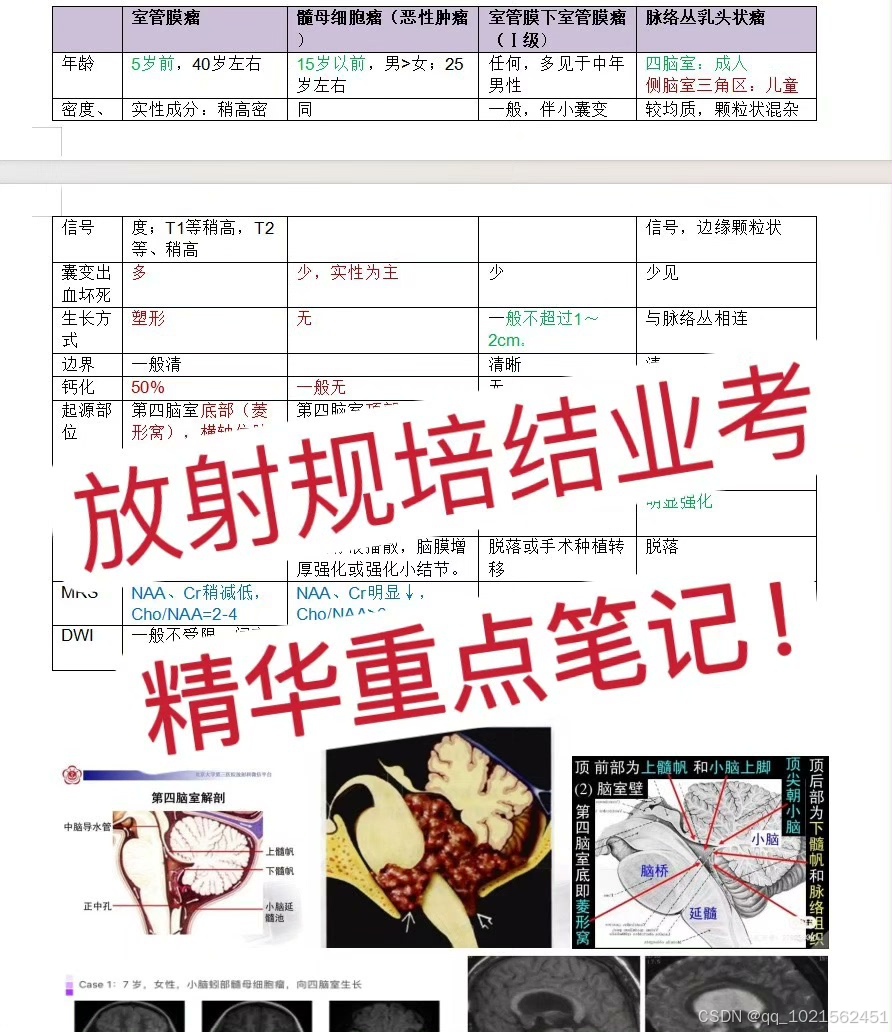

规培结业考试已通过,现分享自己花了大量时间和精力根据考点做的重点笔记,里面包含实际病例影像图片帮助记忆,横向和纵向鉴别诊断表格等,适合看不下去教材,没时间梳理和总结重点的朋友。

笔记来源:最初是为了研究生复试,收集了各个院校的笔试大题和面试专业题题干,然后根据教材的知识点,辅以各种其他书籍、专业公众号整理的答案,这里面不是单纯知识点的罗列,而是结合了实际考题进行了有逻辑的梳理,里面有很多鉴别诊断的表格,还有思维导图。最后背了自己整理的资料,考研面试成绩第一。后面在规培的过程中根据规培大纲和日常写报告的经验,又如法炮制,进一步完善了这份笔记,在规培结业考试的时候就直接省去了看教材这个过程,为我大大提升了效率,缩短了复习时间!!!!